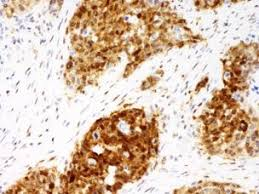

What does strong brown nuclear staining in a p53 IHC indicate?

It indicates Mutant p53, which is stable and accumulates in the nucleus.